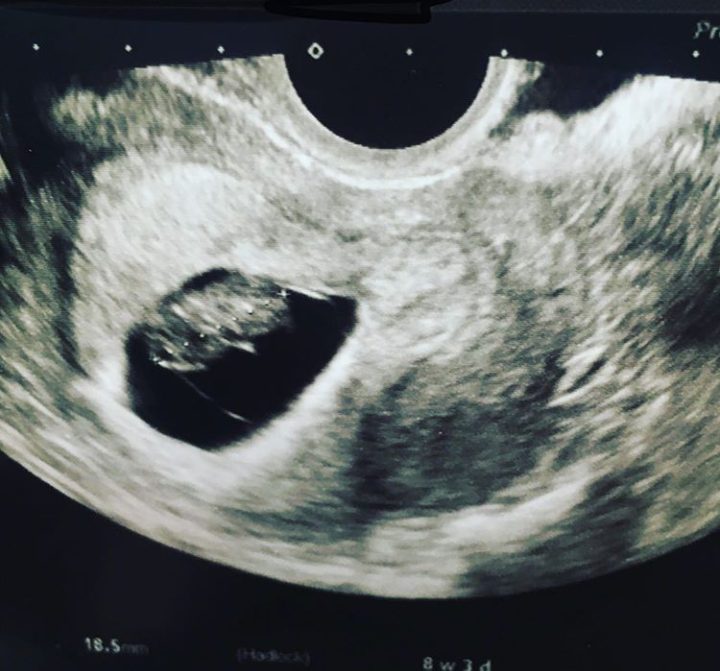

The term infertility is also used to describe the condition whereby a woman is unable to carry pregnancy to its full term. Examples of such cases are miscarriage, recurrent pregnancy loss, stillbirth and many more.

Embryo cryopreservationThis method, also called embryo freezing, is the most common and successful option for preserving a female’s fertility. First, the eggs are removed from the ovaries, fertilized with sperm from her partner or a donor in a lab in a process called in vitro fertilization. The resulting embryos are frozen and stored to be used in the future.

Unlike embryo cryopreservation, in this instance, unfertilized eggs are frozen and stored.